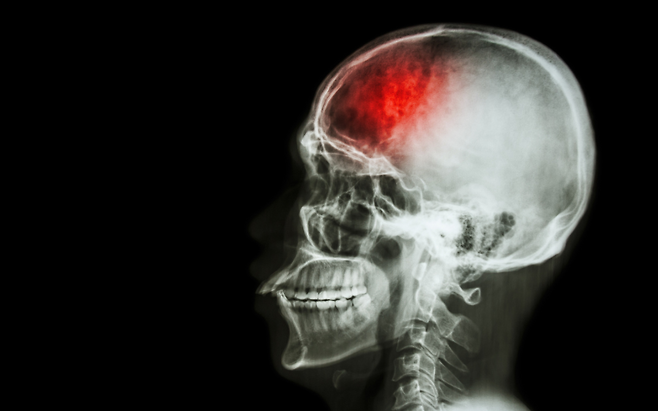

뇌졸중은 갑자기 찾아오지만,사실 미리 보내는 경고 신호가 있습니다. 이 증상을 무시하면,치명적인 결과로 이어질 수 있습니다.

지금부터 뇌졸중 전조 증상 3가지를 알려드립니다.

뇌졸중은 골든타임이 가장 중요합니다. 이런 증상이 나타나면 절대 기다리지 말고, 즉시 병원에 가야 생명을 지킬 수 있습니다.